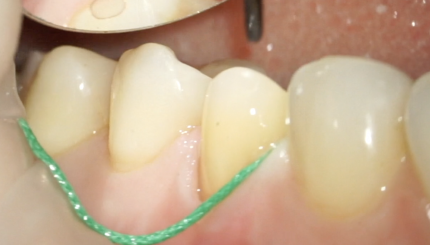

43 42 41 31 32 Финишное препарирование + ретракция

10 августа 2021